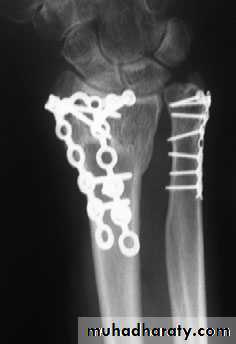

COMMINUTED INTRA-ARTICULARFRACTURES IN YOUNG ADULTS

In the young adult, a comminuted intra-articular fractureis a high energy injury. A poor outcome will result unless intra-articular congruity, fracture alignment and length are restored and movements started as soon as possible. For these patients a much higher standard must be set than would be accepted for the typical osteoporotic fracture. In addition to the usual posteroanterior and lateral x-rays, oblique views and often CT scans are useful to show the fragment alignment. The simplest option is a manipulation and cast. If the anatomy is not restored, then an open reduction may be necessary. The medial complex must be anatomically reduced, which may require open reduction through dorsal and palmar approaches and a combination of wires, plates, screws and bone grafts.